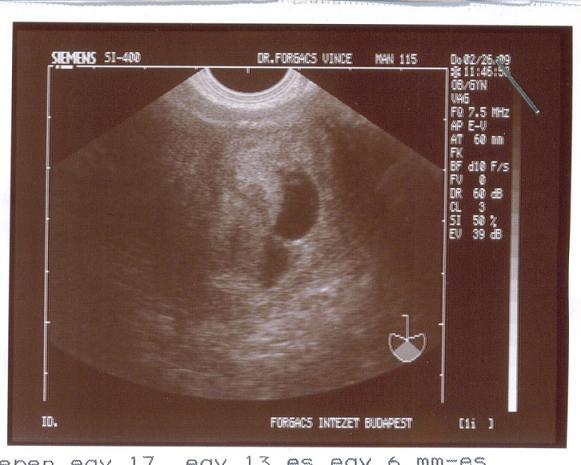

"TVS során a méh üregében egy 17, egy 13 és egy 6 mm-es petezsák látható. A legnagyobb másodlagos szikhólyag és egy élő embrio látható. A középső petezsákban embrionális elem látható, de életjelenség még még nem igazolható. A legkisebb petezsákban embrionális elem nincs.

A méh környezetében kóros képlet nem látható.

Ikerterhesség"

Ja, a doki szerint tuti, hogy nem lesz három babánk. Ketteskét pedig két hét múlva megint megkuksizzák.